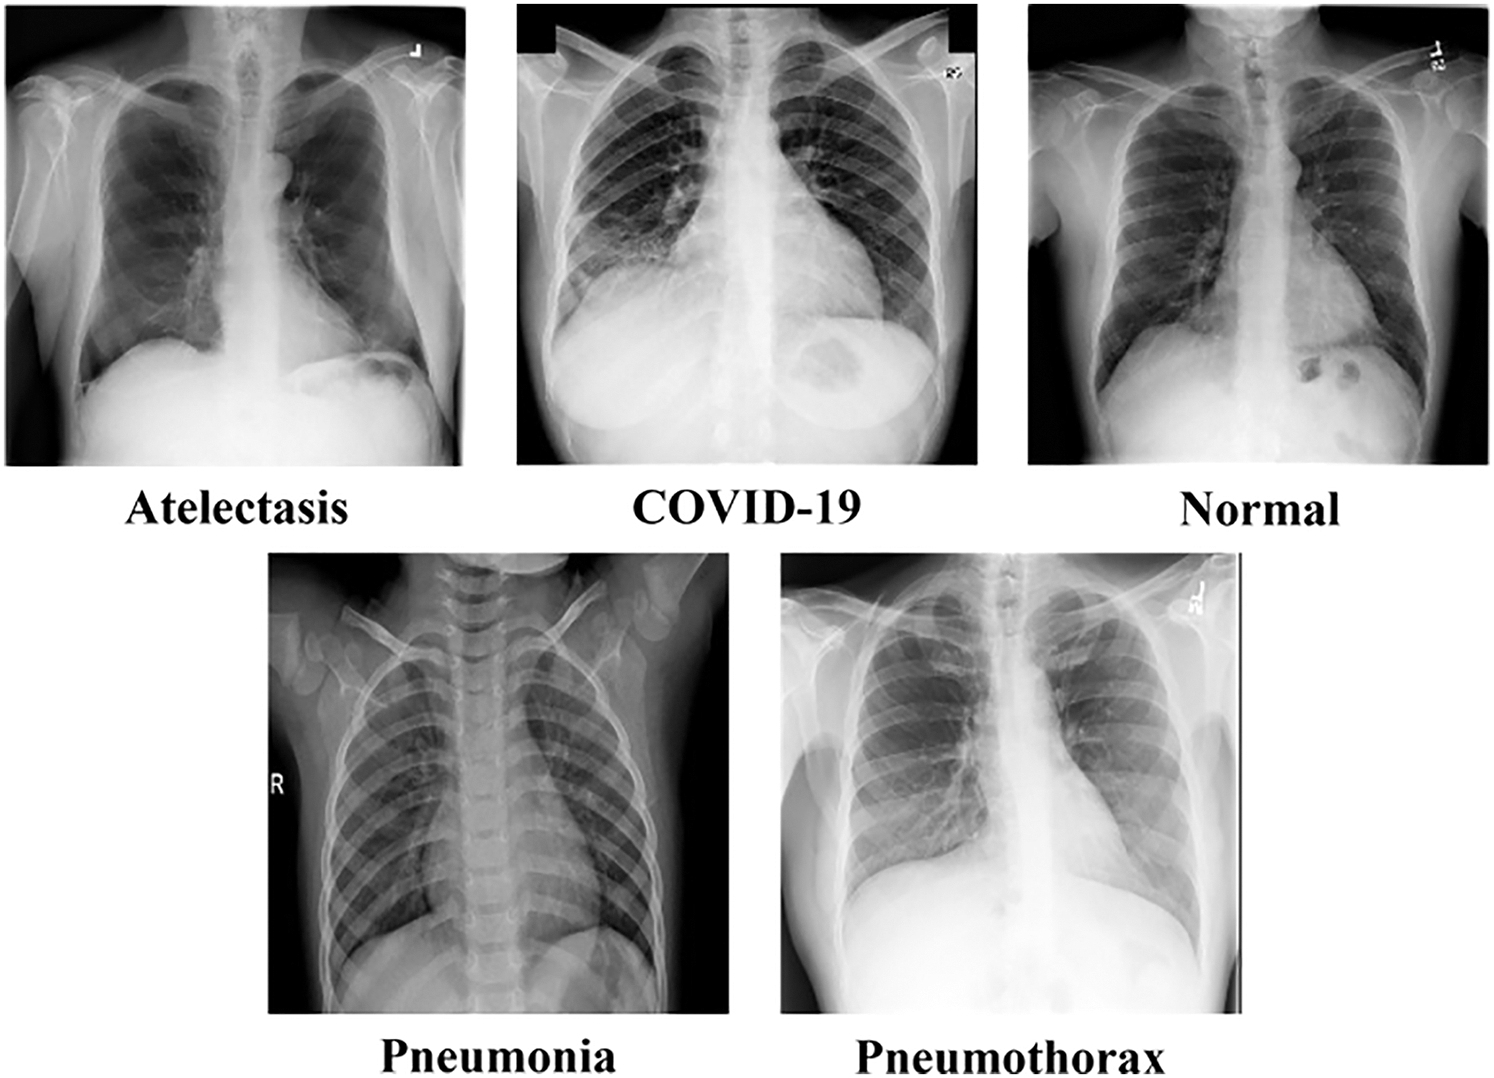

Our dataset consists of chest X-ray images with Posterior Anterior (PA) view as shown in Fig. 2 (more detailed information is provided in Section 3.). We obtained the datasets from reliable online sources such as Kaggle and NIH databases [21–23]. The datasets contain 5 classes which are Atelectasis, COVID-19, Normal, Pneumonia, and Pneumothorax.

Figure 2: Sample images from the dataset containing atelectasis, COVID-19, normal, pneumonia, and pneumothorax classes

The chest X-ray dataset used in our experiments consists of 5 classes which are normal, COVID-19, pneumonia, pneumothorax, and atelectasis. These diseases are well-known and commonly found all around the world. The input images were obtained from online databases at Kaggle (kaggle.com) and the National Institutes of Health (nihcc.app.box.com). Details of the datasets are shown in Tab. 2.